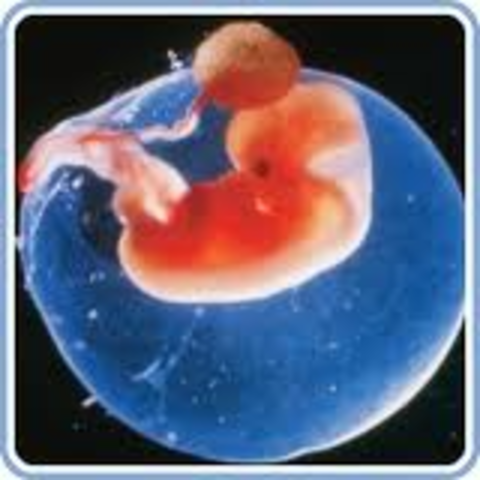

After about 2 weeks the embryo forms and the heart forms in about 3 weeks.

After 8 weeks the embryo becomes known as a fetus.

The yolk sac goes away and the placenta is used, which is the fetus’s life support.